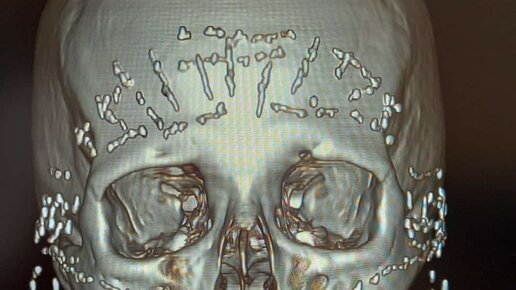

Вот как выглядят ваши «укольчики» и «омоложение». И это необратимо

Сначала я не поняла, что на этом снимке. Его опубликовала моя читательница Ольга, цитирую: «А это немножко жути от знакомой врача КТ)) Пациентка пришла в больницу с жалобами на то, что "лицо поплыло", и нет чувствительности на лице вообще! Из анамнеза - 10 лет безостановочно колола себе "уколы красоты", ботокс, филлеры... И вот он результат... Неврологи разводят руками, как помочь в такой ситуации не знают...» Снимок выглядит вот так: ❗️❗️❗️ ПРЕЖДЕ, ЧЕМ МЕНЯ ПУБЛИЧНО ОКЛЕВЕТАТЬ И ОБВИНИТЬ ВО ЛЖИ, СКАЗАВ, ЧТО СНИМОК ФЕЙКОВЫЙ, ПРОЧТИТЕ ВОТ ЭТО...